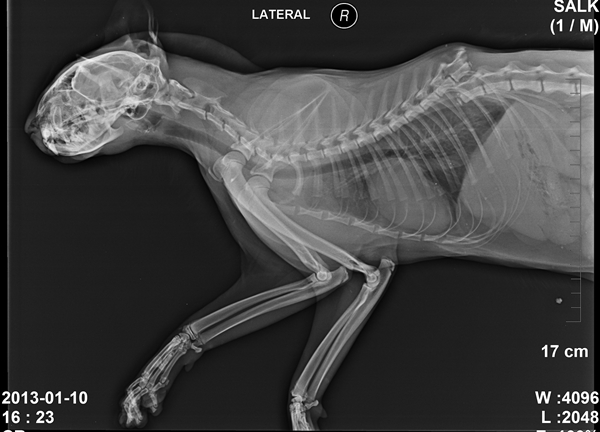

흔히 ‘살쾡이’라고 불리는 삵은 보통의 집고양이와 크기가 비슷하지만 좀 더 늘씬하며 긴 다리를 가지고 있다. 상대적으로 작은 머리와 다소 둥근 귀를 가지고 있는데 눈에서 귀까지 어두운 색의 줄무늬가, 눈에서 코까지는 흰색의 줄무늬가 존재한다. 영어이름인 ‘leopard cat’에서 알 수 있듯이 몸 전체의 털은 표범(leopard)처럼 갈색 바탕에 검정색 반점들을 가지고 있다.